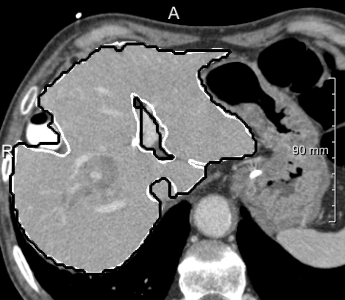

Example segmentations of the 2D U-net ensemble (2 mm) are illustrated in 3. Contour precision is limited by the resampling, but the model nicely excludes the vena cava and large hilar vessels much like in our training set. This hinders comparison against the state-of-art, since the reference masks from the SLIVER07 challenge (dashed in 3, right) partially include these vessels.

In most cases, the purely slice-wise application of the 2D U-net (dashed contours in 4) does not show any comb artifacts in orthogonal views. However, the ensemble classifier (solid contours) performs significantly better when the appearance is severely abnormal and 3D context is needed. In some cases, it locally performs worse, but has an overall better volumetric overlap (Wilcoxon signed-rank test, ). The ensemble models performed significantly better than the purely 2D transversal model on the same voxel size.